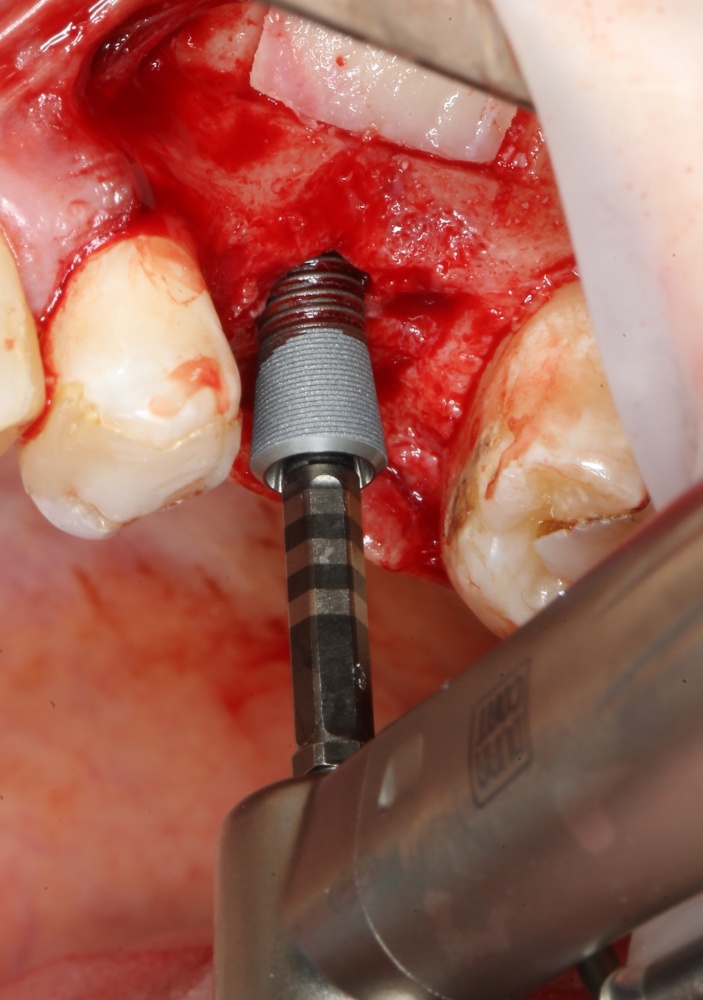

Приступаем к установке имплантата.

Кстати, комплект поставки не содержит ни заглушки, ни абатмента. А сам имплантат фиксируется на ключе простым заклиниванием платформы. Т. е. не слишком надёжно:

Если лунка подготовлена правильно, то имплантат проваливается в неё почти полностью: